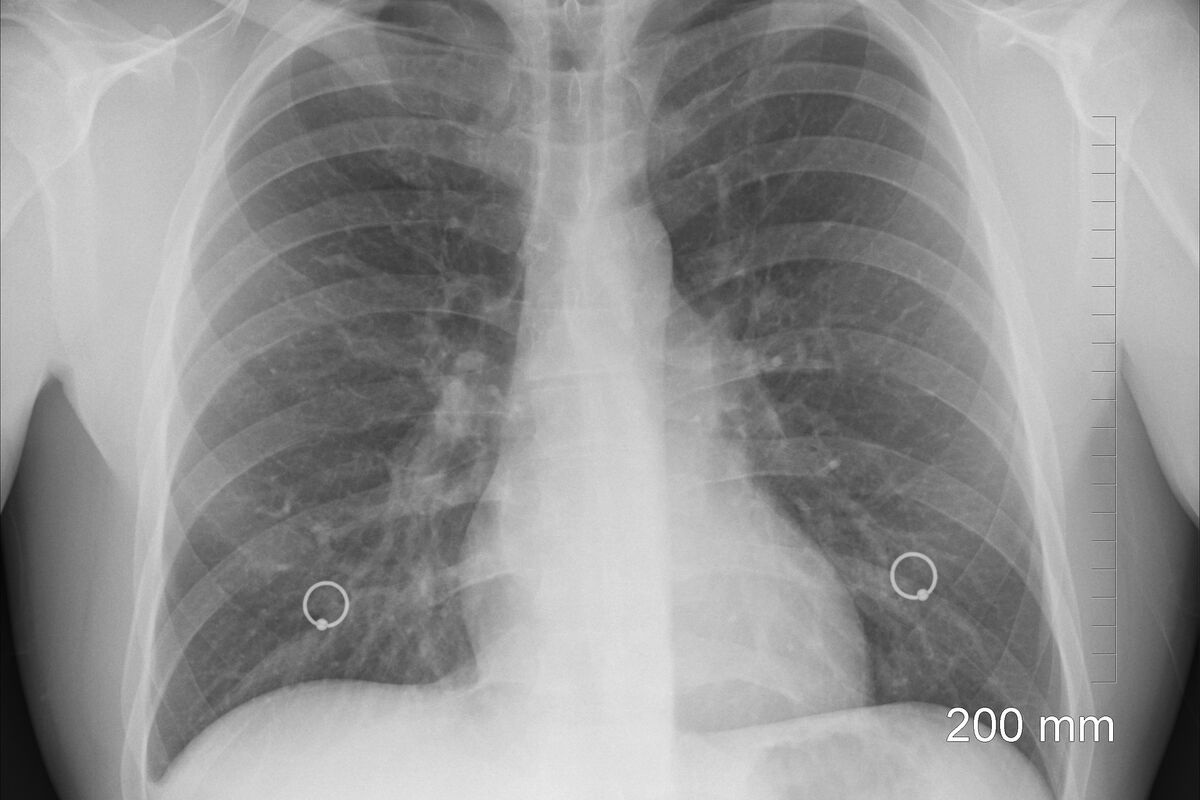

Ilustracija, Foto: Pixabay